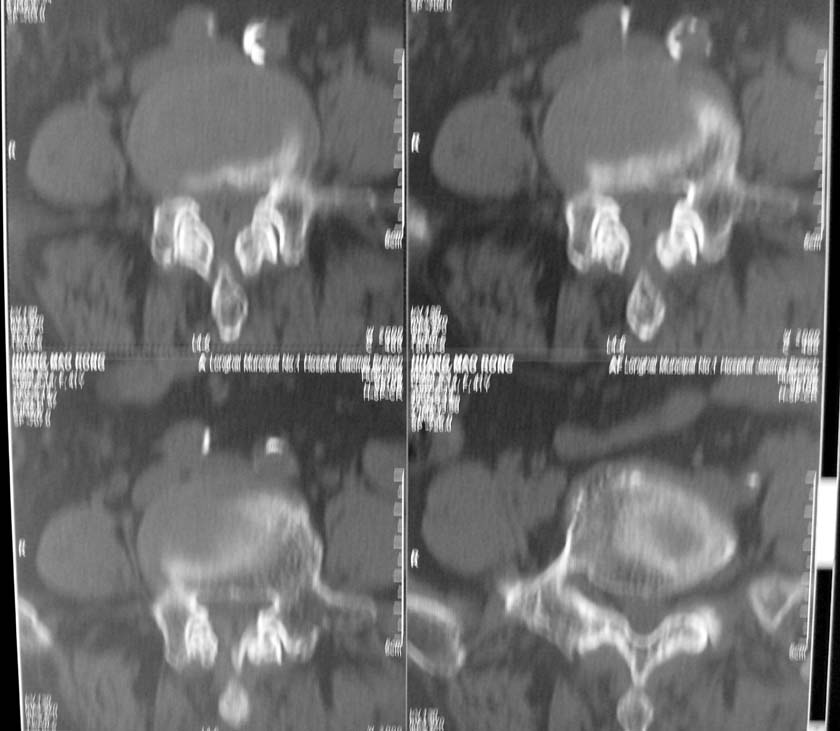

以下是引用jiangjing在2007-5-16 11:05:00的发言:[br]zhichi [br]ct所见:[br]l4-5椎间盘膨出,双侧黄韧带增厚,致使对应椎管变窄,硬膜囊受压.[br][br]l5-s1椎间盘后突,其后硬膜囊受压.l3-4椎间盘未见突出征象.[br]诸椎体边缘及对应椎小关节突骨质增生.腰椎生理曲度正常.[br]腹主动脉壁广泛钙化.[br]印象:[br]1、l4-5椎间盘膨出并双侧黄韧带肥厚及椎管狭窄。[br]2、l5-s1椎间盘突出。[br]3、腰椎及椎小关节退变。